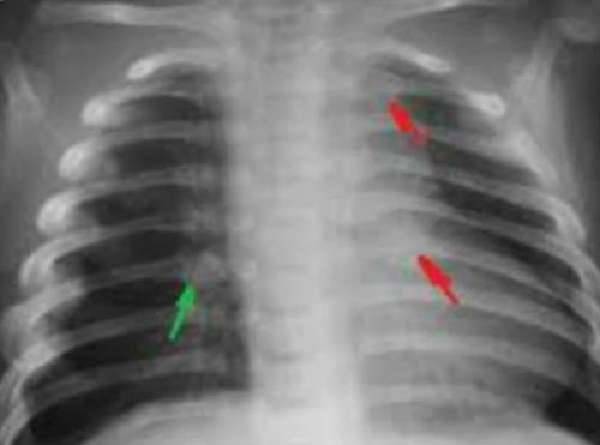

Плеврит — скопление воспаленной жидкости в правой плевральной полости, является осложнением пневмонии, признаком туберкулеза легких. Раздражение плевральных листков вызывает сильную боль сзади в области нижних ребер и в подреберье с иррадиацией в живот, невозможность глубокого дыхания, одышку, отставание правой стороны грудной клетки в акте дыхания.

На рентгеновском снимке видна жидкость в плевральной полости справа, чтобы точно узнать причину плеврита необходимо сделать повторный снимок после ее удаления

У пациентов общее тяжелое состояние, выраженная интоксикация, ознобы, высокие скачки температуры. Плеврит может быть вызван абсцессом легкого, раковой опухолью, нагноившимися бронхоэктазами.